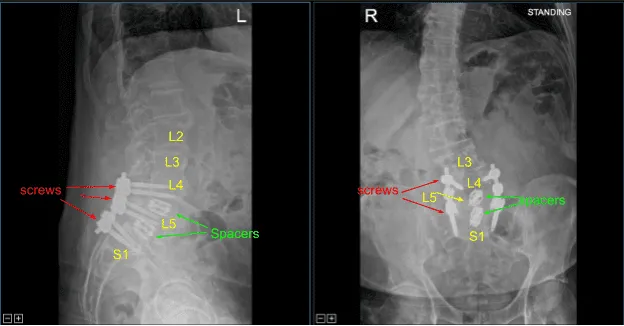

Precut titanium rods were contoured with rod benders and placed across the screw tulips from L4 to S1and secured with locking caps which were all final tightened with a torque and anti torque device. Final AP and lateral x-rays showed correct and complete hardware implantation.

The patient was followed up two weeks after their surgery and then continued to follow up in our office 4, 6, and 8 weeks after the surgery. The patient showed gradual signs of improvement with lumbar spondylolysis, spondylolisthesis and spondylotic radiculopathy.

Post Op X-ray